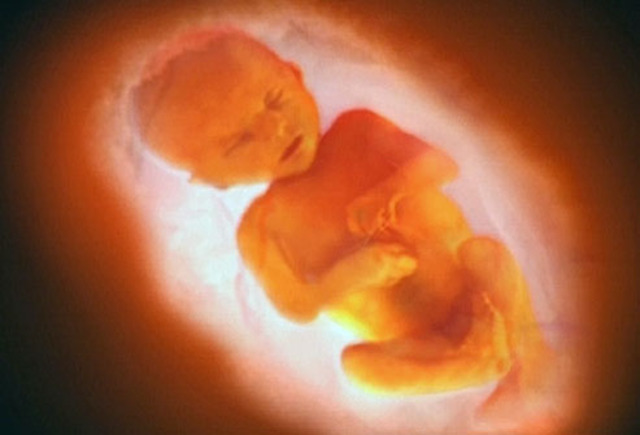

• week 12 of the fetal development

week 12 of the fetal development

the face and it's features are well formed. The head makes up nearly half of the fetus' size. Tooth buds appear.